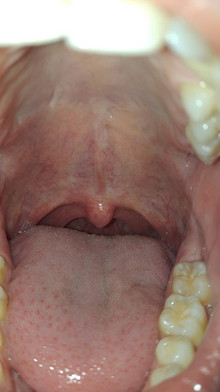

#uvula